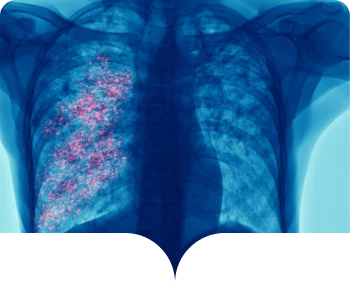

es un virus frecuente que infecta la nariz, la garganta, los pulmones y que generalmente causa síntomas leves

y similares a los de un resfriado.1,2

Algunas personas, especialmente los adultos mayores y los bebés menores de 6 meses, pueden necesitar hospitalización. El VSR puede causar bronquitis (inflamación de las vías respiratorias pequeñas en el pulmón) y neumonía (infección en los pulmones).1,2